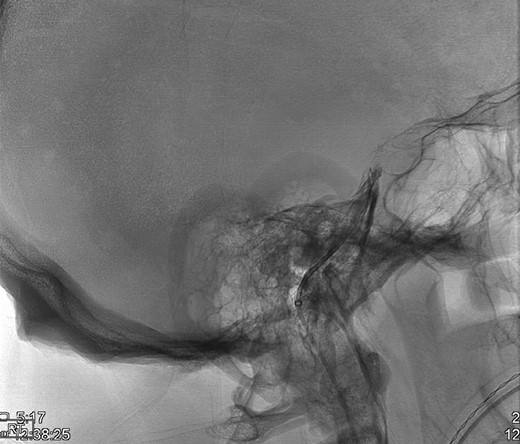

Upon the unimpressive decrease in HbA1C despite an appropriate increase in medical therapy, Cushing’s syndrome was suspected and diagnostic work up was pursued (Fig. 1). A dexamethasone suppression test as well as a late night salivary cortisol test showed abnormal results. The late night cortisol test showed high values congruent with the range necessary for diagnosis of Cushing’s syndrome (>7.5 mcg/dl) [3]. These findings were suggestive of ACTH-dependent Cushing’s syndrome. At this point, an MRI of the brain with sella protocol was ordered and showed no evidence of a pituitary adenoma or pituitary etiology (Fig. 2). Bilateral inferior petrosal sinus sampling was performed (IPSS) and the results were highly suspicious for pituitary microadenoma located more on the left side of the gland, with some activity also present on the right side (Fig. 3). The peak IPSS ACTH value was 1031 pg/ml. A repeat MRI of the brain with sella protocol with higher resolution (3 T MRI with sella protocol with thin cuts) was done in order to visualize the lesion for surgical planning, which did not show any pituitary lesion. FSH, LH, prolactin, insulin-like GF-1, TSH, free T4 and testosterone labs were ordered, and all were within normal limits.

Testing to establish the cause of Cushing’s syndrome Reproduced with permission from: Nieman LK. Establishing the cause of Cushing’s syndrome. In: UpToDate, Post TW (Ed), UpToDate, Waltham, MA. (Accessed on [Date].) Copyright © 2019 UpToDate, Inc. For more information visit www.uptodate.com.